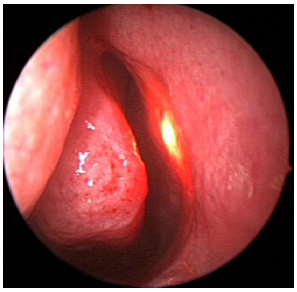

E-DCR Type 3 (UP in pre-lacrimal position) (Figure 3c): inferior uncinotomy is required to find the natural ostium of the maxillary sinus. Then, via a gentle dissection, the vertical portion of the UP is removed. In this way, the lacrimal bone is exposed and drilled under light guidance. Finally, the lacrimal sac is marsupialized. After any of the described procedures, with the opening of the lacrimal sac, the lacrimal system is irrigated with antibiotic solution and then a bicanalicular silicone intubation is performed.

Figure 3c UP in lacrimal position.